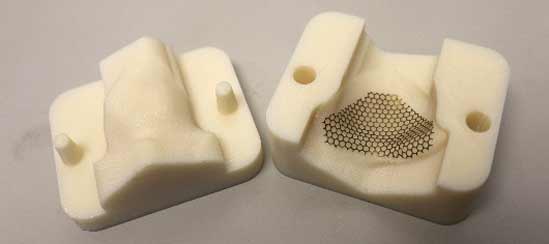

Traditionally ophthalmic surgeons would create the implant from either a titanium mesh, a thin piece of porous polyethylene or a combination of both, and manually insert into the subperiosteal space after all unstable bone fragments have been removed and the prolapsed tissues is reduced.

Now Hong Kong Polytechnic University’s Industrial Center (IC) is using 3D printed models to improve eye orbital implant surgery accuracy and reduce operating times. IC uses a Fortus 3D Production System from Stratasys to create customized molds for the orbital implants, in just three to four hours.

Using a patient’s CT scan and X-ray images, the IC team reconstructs the patient’s orbital floor in CAD software. They then 3D print two thermal layers – the upper and lower parts of the mold – and press a thin titanium sheet between the two mold parts to form the shape. This precision helps ophthalmologists create accurate implants before an operation and is expected to be particularly beneficial in complicated cases like complex fractures involving multiple orbital walls and rims.

“Surgeons would only need to sterilize the mold and form the implant shape by pressing the two parts together, resulting in an accurate customized implant,” said Louis Sze, assistant engineer at the Hong Kong Polytechnic University.